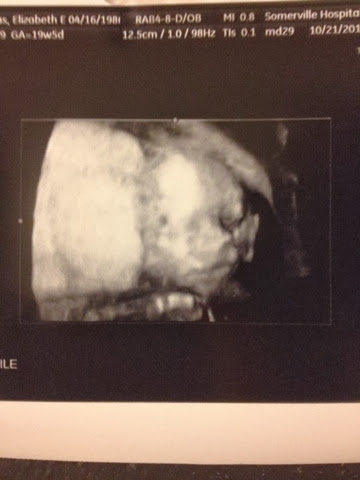

Best ultrasound ever!!

Today we had our 20 week anatomy scan and it could not have gone better! I was so nervous with all the horror stories I've heard about silent techs and straight faces, but our tech, Mae, was the sweetest, warmest woman. For two first time parents who were nervous wrecks, she just eased our mind completely. She kept saying how everything looks perfect and beautiful-it was music to our ears!

And of course it was just amazing to see our little one in action. He or she is quite the mover & shaker!

It was hands down the best thing I've ever seen in my whole life!!